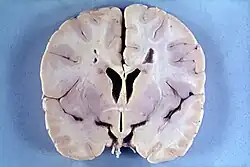

Die Alexander-Krankheit (Morbus Alexander) ist eine seltene Erkrankung aus der Gruppe der Leukodystrophien. Es handelt sich um eine genetisch bedingte Störung, bei der eine fortschreitende Degeneration der Weißen Substanz von Gehirn und Rückenmark auftritt. Klinisch macht sich die Alexander-Krankheit häufig bereits im Kleinkindesalter mit einer Verzögerung der psychomotorischen Entwicklung und einer Zunahme der Schädelgröße bemerkbar. Ursache der bei der Erkrankung auftretenden strukturellen Veränderungen der Stützzellen des Gehirns (Astrozyten) und einer Entmarkung sind meist spontan auftretende dominante Mutationen des GFAP-Gens, das für ein astrozytäres Strukturprotein, das saure Gliafaserprotein, codiert. Eine Heilung der Krankheit ist nicht möglich. Erkrankte Kleinkinder überleben in der Regel das sechste Lebensjahr nicht.

Die Alexander-Krankheit ist primär eine Erkrankung der Astrozyten, Stützzellen des Gehirns (Glia), deren Intermediärfilament GFAP fehlerhaft gebildet wird. Zusammengelagert mit anderen Proteinen bilden sich astrozytäre Einschlüsse, die als Rosenthal-Fasern bekannt sind. Feingeweblich sind Rosenthal-Fasern bei der Erkrankung im gesamten Zentralnervensystem (Gehirn und Rückenmark) nachweisbar, finden sich jedoch bevorzugt periventrikulär und in der Umgebung von Blutgefäßen. Elektronenmikroskopisch zeigt sich eine enge Verbindung der Rosenthal-Fasern mit Intermediärfilamenten.

Darüber hinaus findet sich bei Kindern eine mangelhafte Myelinisierung und bei älteren Patienten eine Entmarkung. Dabei sind sowohl sensorische als auch motorische Nervenfasern betroffen. Die Myelinisierungsstörung wird insbesondere bei kleinen Kindern häufig von einer Makrozephalie und manchmal von einem Hydrozephalus begleitet.

Das Verteilungsmuster der entmyelinisierten Areale stimmt nicht mit dem der Rosenthal-Fasern überein; Myelinisierungsstörung und Faserbildung scheinen also voneinander unabhängige Manifestationen der Krankheit zu sein. Es wird angenommen, dass Veränderungen der Astrozyten sekundär zu einer Myelinisierungsstörung führen.